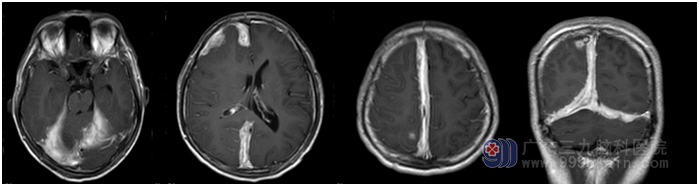

入院后查头颅MR提示:1.大脑镰右侧,小脑幕两侧、右侧额部及右枕部幕下多发硬膜外脓肿形成,右侧顶叶多发脑脓肿,考虑来源于右侧中耳乳突炎所致可能;2.右侧大脑镰下疝合并小脑扁桃体下疝形成;3.垂体变薄,考虑与颅内高压有关可能。

排除手术禁忌症后于2016-07-01行双侧脑脓肿钻孔引流术,术后予反复冲洗引流后,脓液最终引清,患者症状明显改善,后续患者转院进一步行右耳胆脂瘤型乳突炎治疗。